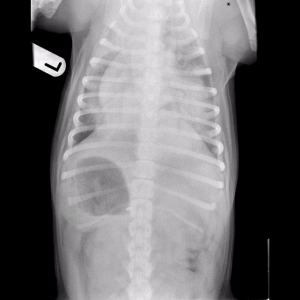

A chest X-ray taken by the referring vet showed a diffuse, severe, alveolar pattern bilaterally. A diagnosis of noncardiogenic pulmonary oedema was made, and Bella was treated with oxygen supplementation. Once she was more stable, a CT scan of the thorax was performed and showed no other underlying disease or airway obstruction.